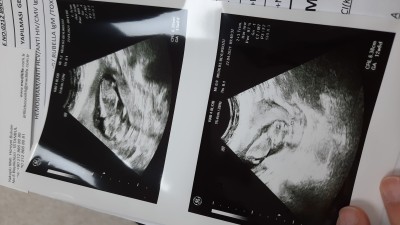

Kızlar doktor büyük ihtimalle erkek ama değişebilir de bu haftalarda yanılma payı oluyor dedi :) Bi tane presnsesim vardı sanırım bi tane de prensimiz olcak ama değişedebilir :)

İkizler mi maşAllah kaç haftalıksın

Yok canım tek gebelik :) 13 haftalık tam :)

Aynen erkek cnm. Crl si düşük çıkmış

Düşük çıkınca erkek mi oluyordu ben kız diye hatırlıyodum acaba döner mi sonra dedim :)

Benim iki oğlumda da 12-15 haftalık iken 5 ila 7 Cm arasında idi. Ablamın kızları var 2 tane. Onunki de hep yüksek idi. 68-70 falan yani

Inşallah canım benim kızda da 13 haftalıkken kıza benziyor demişti sonra değişmedi ama bu değişir mi bilmem. Yüz üstü yatıyordu kerata :))